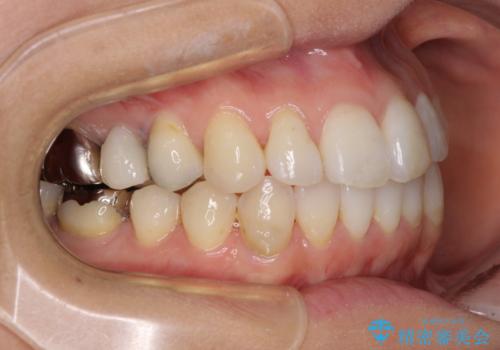

- 捻れた前歯と目立つ銀歯を気にして来院された患者様です。

歯列不正は軽微であったため、インビザライン・ライトにて改善することとしました。

左下大臼歯は根管治療が必要であったため、矯正治療前に根管治療を行い、その後矯正治療を行うこととしました。

矯正治療後には期にある銀歯を全てセラミッククラウンなどで補綴治療することとしました。

インビザライン・ライトによる矯正治療であったので、時間をかけずに治療を終えることができました。

口を開ける度に目立っていた銀歯もセラミックで自然な口元の印象となりました。